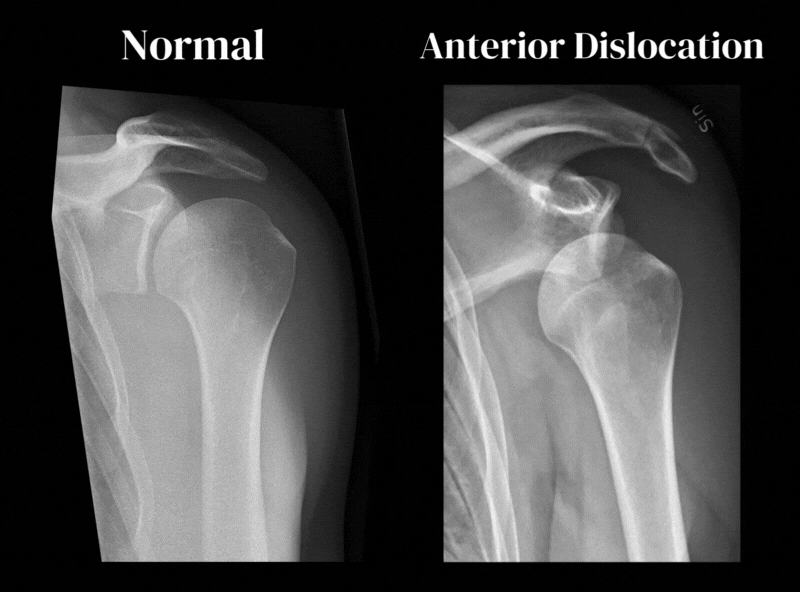

A luxação anterior é a mais comum, representando cerca de 90% dos casos. Neste caso, a cabeça do úmero se desloca para a frente da cavidade glenoidal, geralmente após uma queda com o braço estendido ou um trauma em posição de abdução e rotação externa.

A diferenciação entre esses dois tipos é essencial, pois influencia tanto o diagnóstico em exames de imagem quanto as estratégias de redução e reabilitação.

Para confirmar o diagnóstico e verificar se há fraturas associadas, costumamos utilizar o raio-x, que mostra claramente se o úmero saiu da cavidade glenoidal.